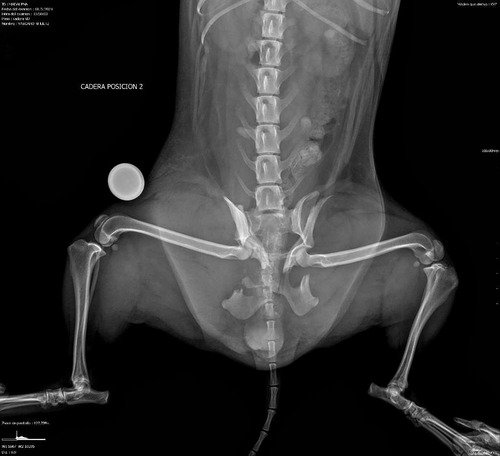

No dia 18/05 ela foi brutalmente atropelada, e teve parte da sua pélvis destruída. São muitas fraturas nos ossos do quadril, lesões na bexiga, compressão do intestino e muitos cortes no corpo todo.

Felizmente ela está estável e o seu quadro é reversível mediante cirurgia de reconstrução dos ossos. A cirurgia é bem complexa e delicada, devido ao porte da Madalena (pesa apenas 4 kilos)

Já realizou exames de ultrassonografia do abdômen, radiografias, exames de sangue, eletrocardiograma e o pré cirúrgico.